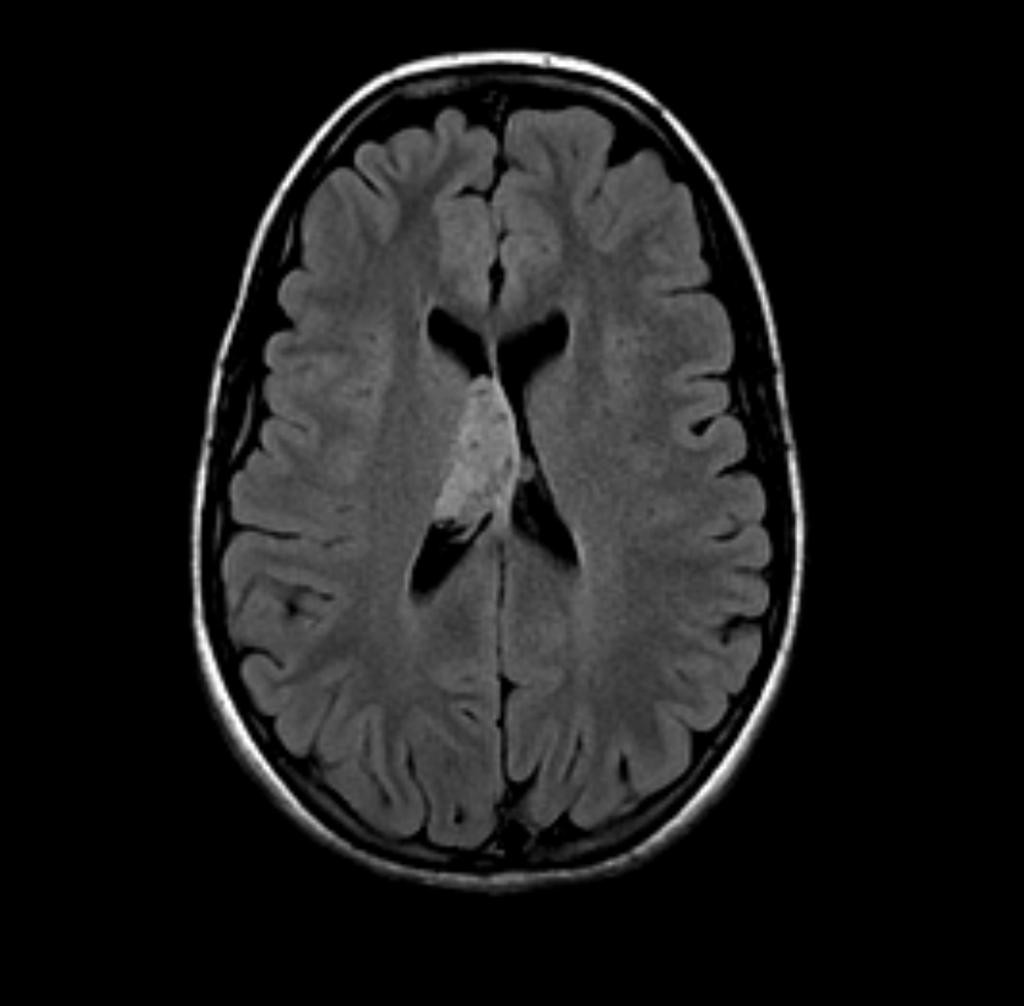

Neurocytome central

• Corne frontale ou corps des VL inséré sur le septum pellucidum

• Masse polylobée, kystique, calcifiée 50 à 70%

• IRM

• T1 hétérogène, masse iso et kyste hypo

• T2 hétérogène en « bulles de savon«